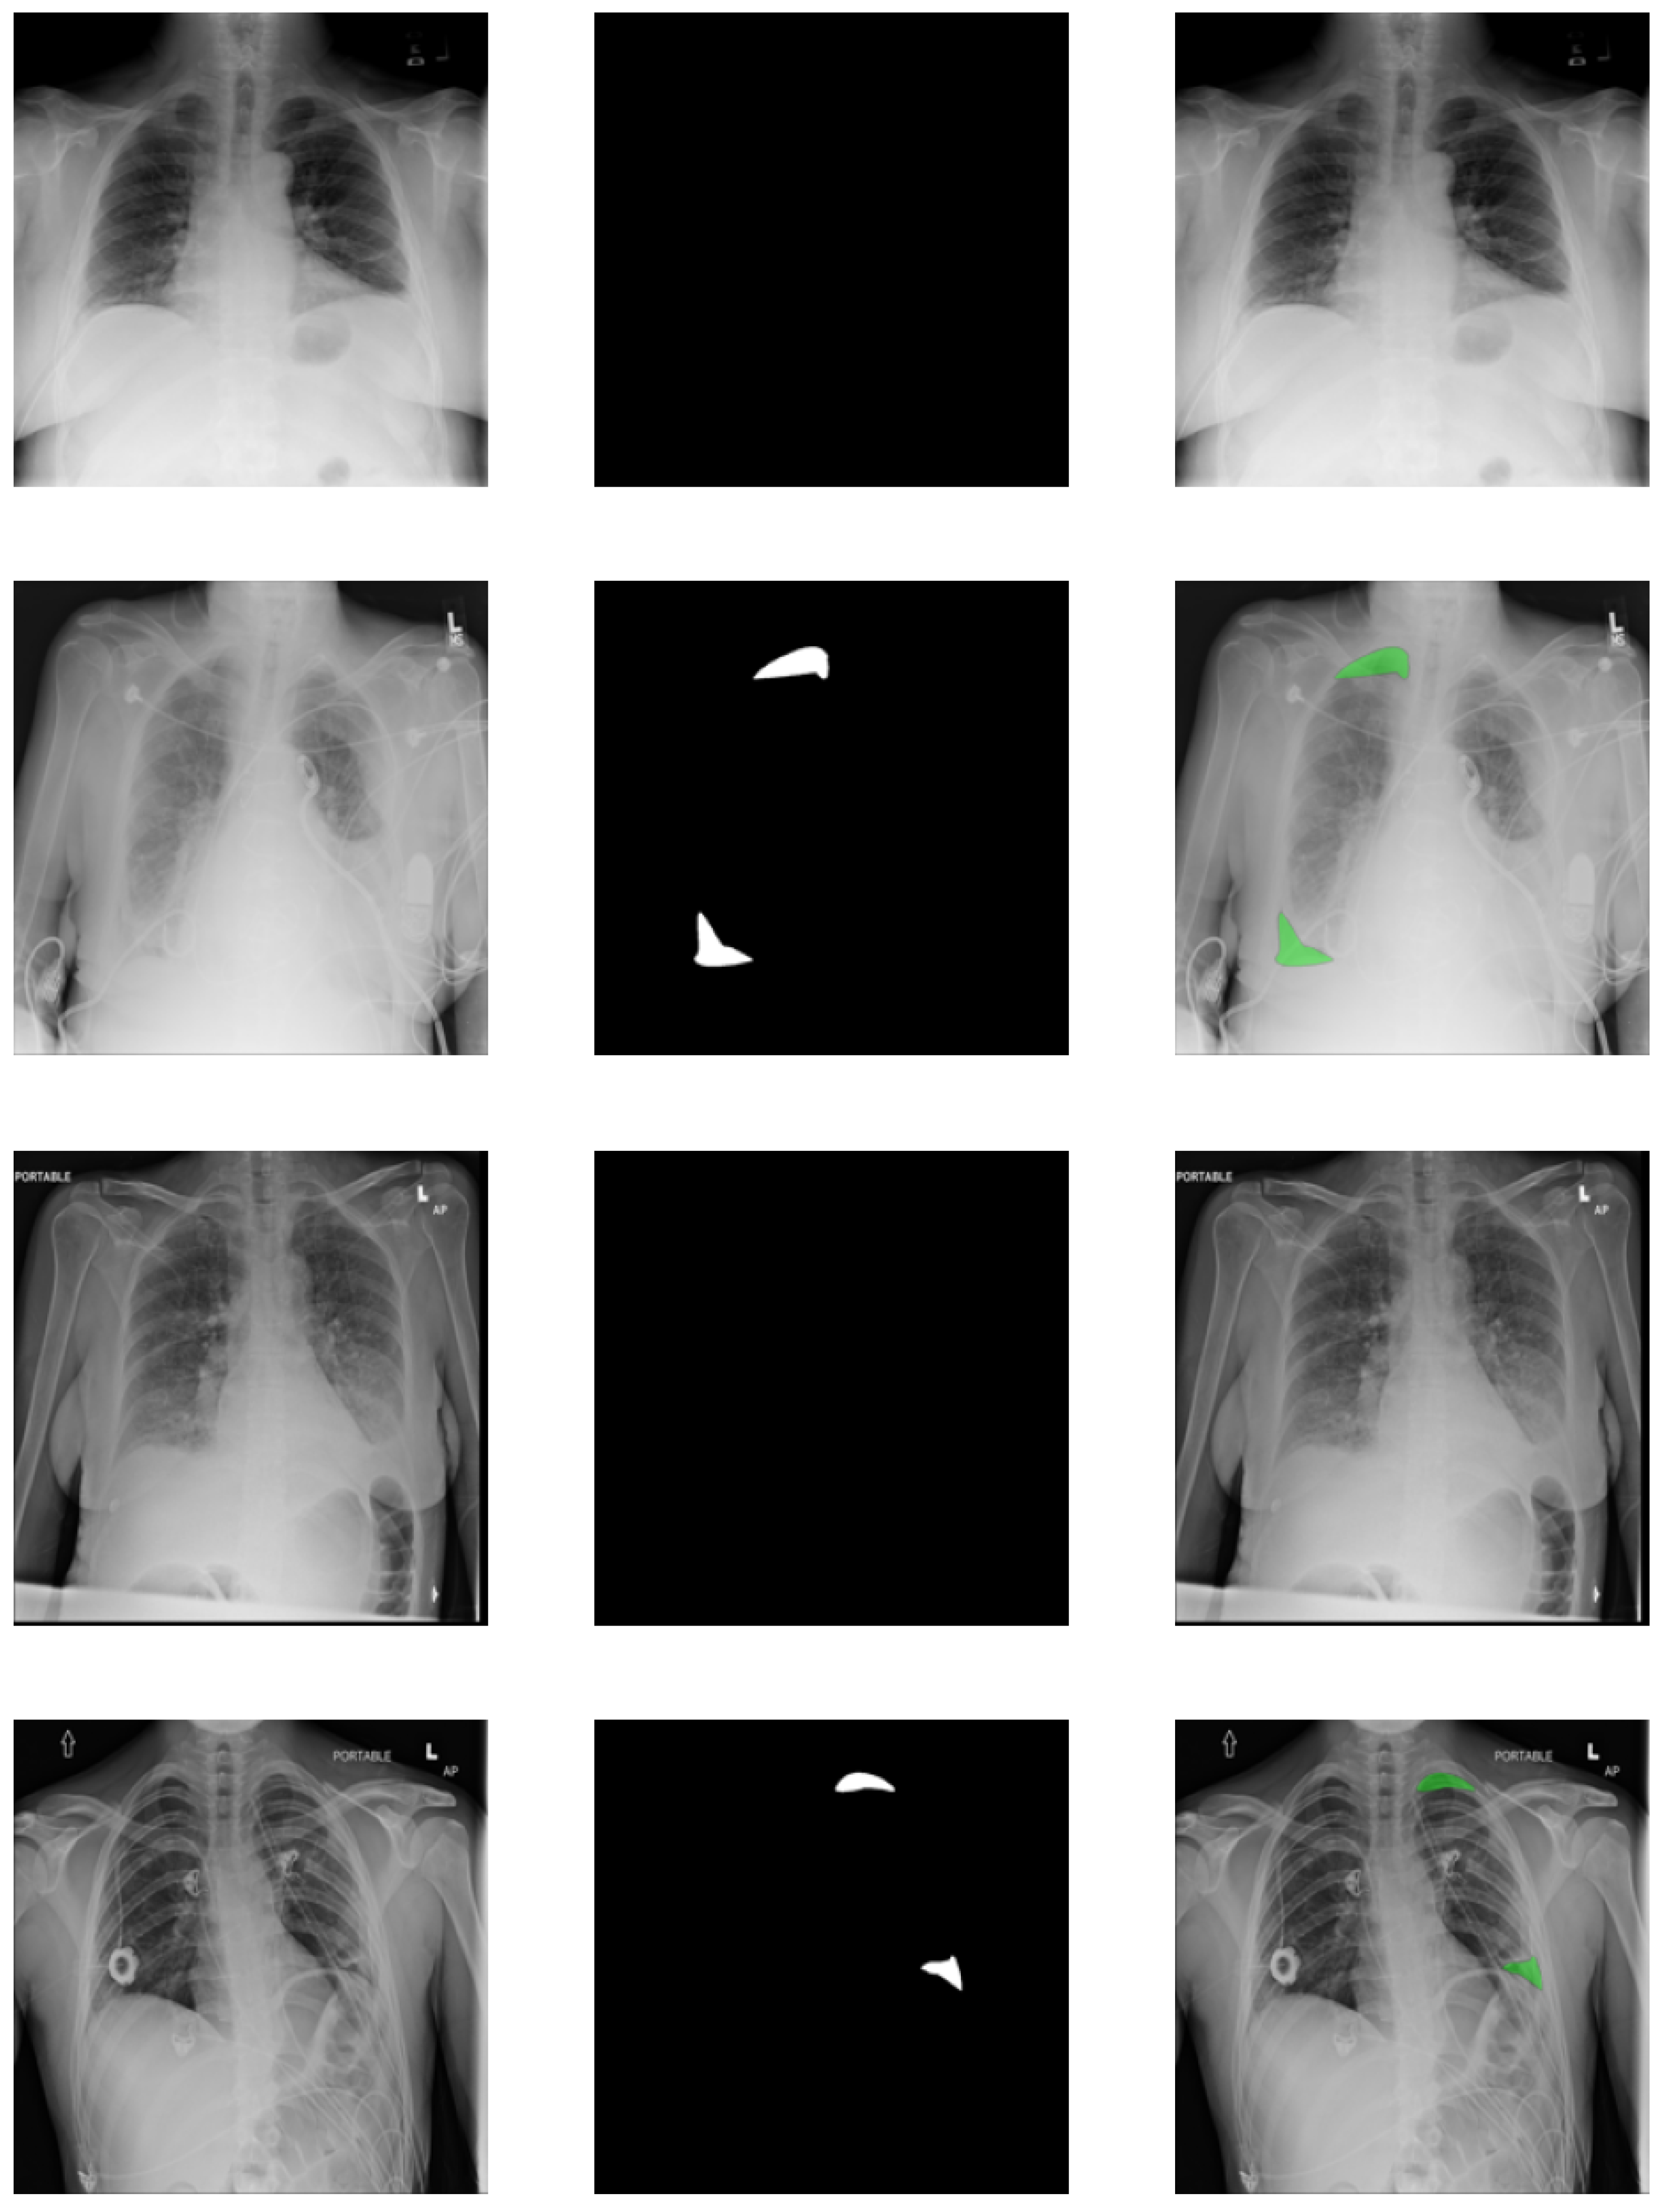

To show that our method works in general, a completely different dataset was selected: SIIM-ACR Pneumothorax containing chest X-rays. This dataset was created for a Kaggle challenge by taking the ChestX-ray14 dataset released by the National Institutes of Health (NIH) [50] and creating pixel-level annotation segmentation masks for images with positive pneumothorax (collapsed lung). The pixel-level annotations were created by the experts specifically for the challenge. Some of the examples can be seen in Figure 5. The final dataset consists of 9378 negative images and 2669 positive images. The size of the original images is 1024 × 1024 , but to simplify the models and speed up training, all were resized to 224 × 224 to be the same size as images from the first dataset so that the topologies could be identical.

As mentioned before, pixel-level annotations were created for all positive classes. The pixels of the regions containing the signs of pneumothorax are marked with the value 1 and everything else is marked as 0. These were then used as the segmentation masks in the reconstructions. For negative images, an empty array of zeros was used as the target, because there are no traces of pneumothorax anywhere.

In addition to the classification, C-CapsNet models generate reconstructions of the specified targets. Several examples of these can be seen in Figure 11. The first column shows the input images for all models, the second the output of the best-performing original image reconstruction model, the third column shows the segmentation masks of these images, and the final column shows the outputs of the best-performing segmentation reconstruction model. These four examples were chosen, as they best represent the usual cases on other data. The false negative images have no segmentation and the false positive have random regions highlighted.